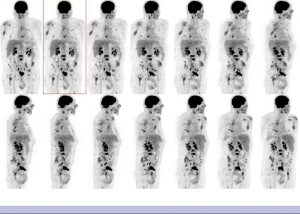

Bilan d’extension d’un myelome multiple.

Contexte de fracture de la diaphyse humérale droite ostéosynthésée il y a 10 j. Cimentoplastie L3 et L4 il y a 8 jours. Ostéosynthèses sur le rachis cervical et dorsal il y a un mois

Multiples foyers hypermétaboliques et lytiques disséminés sur le rachis, les côtes, le bassin.

Atteinte du mur postérieur de D8, du col fémoral droit avec un risque fracturaire élevé à ce niveau.